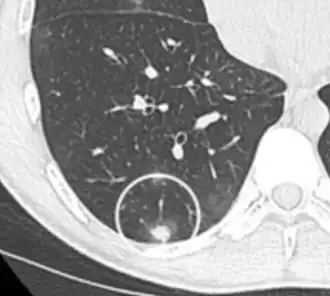

- Vascular convergence is where vessels converge to a nodule without adjoining or contacting the edge of the nodule, and is mainly seen in peripheral subsolid lung cancers.[9] It reflects angiogenesis.[9]

Air bronchograms is defined as a pattern of air-filled bronchi on a background of airless lung, and may be seen in both benign and malignant nodules, but certain patterns thereof may help in risk stratification.[9]